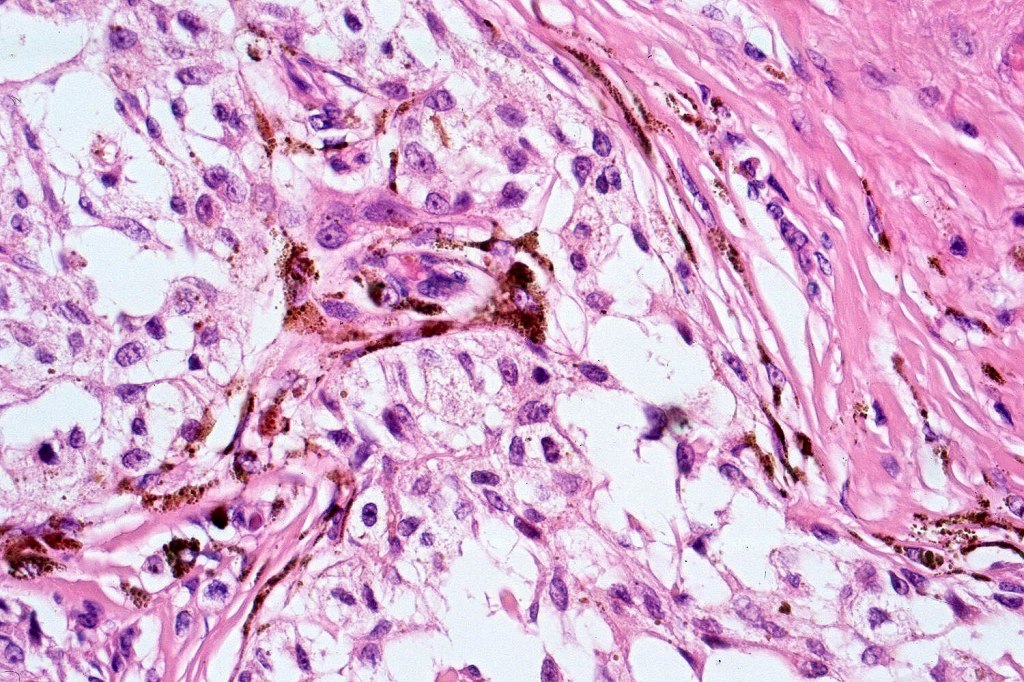

Histologically, it is characterized by a dense population of spindled, dendritic melnanocytes & melanophages with variable fibrosis. It may sometimes represent a component of a combined nevus. Mitotic activity is not usually present and pleomorphism is absent (see atypical blue nevus below). Involvement of the arrector pili muscle is not uncommon.

•Admixture of spindle cells, pigmented bipolar or dendritic cells & melanophages

•Cytoplasm is pale and nuclei are small with inconspicuous nucleoli

•Multinucleate giant cells sometimes present

•Stromal fibrosis, myxoid change, vascular hyalinization with cyst formation are often seen

•Some tumors are composed spindle cells in a fascicular or neuronevoid pattern

•Perineural involvement may be seen

Atpical blue nevus

This is exceedingly rare and the diagnosis should be used very sparingly. It is likely quite benign although very occasionally, a sentinel node biopsy is positive. Great care must be taken to make sure that a blue nevus-like melanoma isn’t missed. It shows the low power features of a blue nevus but high power scrutiny reaveals pleomorphism, nuclear hyperchromatism and increased mitotic activiy (<1 sq mm). Abnormal mitoses are absent as is necrosis. Perineural involvement can be seen but lymphovascular invasion is absent.